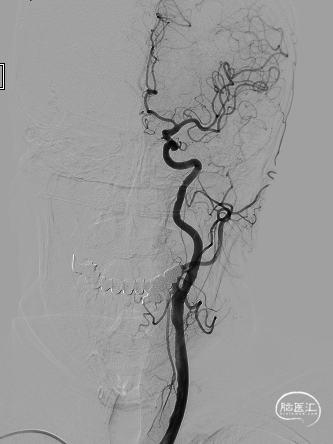

➢ 脑血管造影检查

患者主因言语不利3天入院,头核磁提示右侧额、顶叶多发低灌注梗塞,脑血管造影提示右侧颈内动脉开口重度狭窄,为责任血管,另外患者前交通动脉、右侧后交通动脉开放不良,并且狭窄严重,考虑到高灌注风险,决定分期处理,一期小球囊扩张改善供血,二期支架成型。